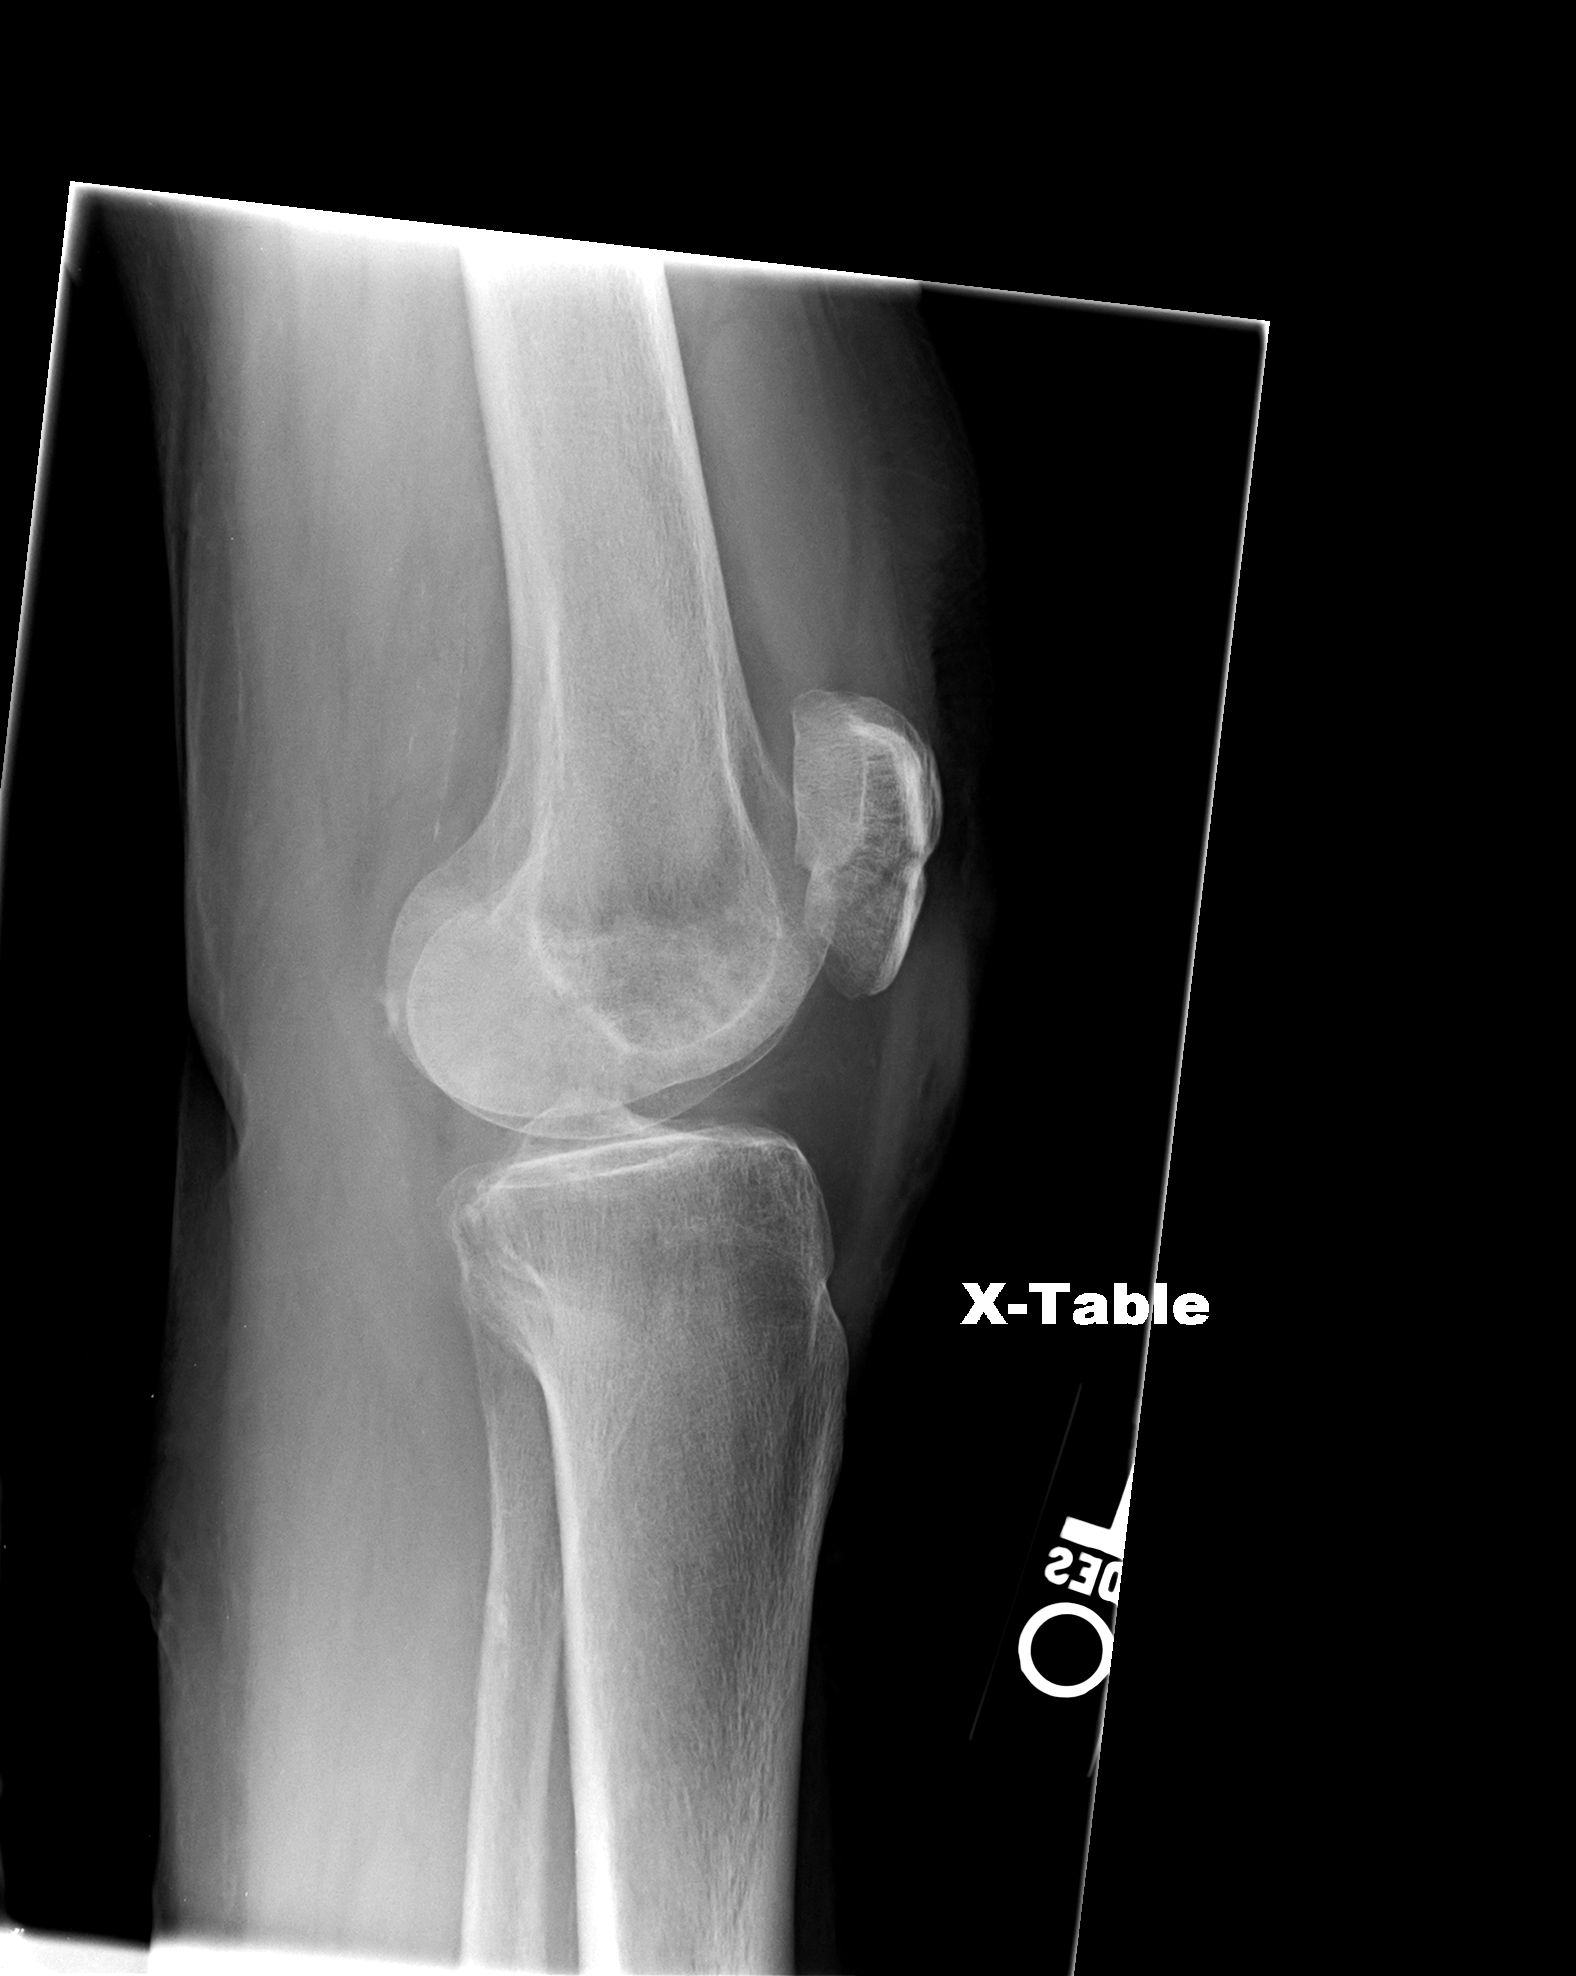

Xray images showing real fracture of broken leg bone under the knee Broken Knee X-Ray The doctor may put mild pressure on the kneecap, and may bend or straighten the leg to see if those actions cause or increase pain or reveal a deformity. Symptoms of a knee fracture include pain, swelling, and bruising at the site of injury; Patella fractures are traumatic knee injuries caused by direct trauma or rapid contracture of the quadriceps. Broken Knee X-Ray.

Knee Xrays Broken Knee X-Ray It’s usually caused by direct. The doctor may put mild pressure on the kneecap, and may bend or straighten the leg to see if those actions cause or increase pain or reveal a deformity. Symptoms of a knee fracture include pain, swelling, and bruising at the site of injury; And difficulty bearing weight to walk or stand. Patella fractures are. Broken Knee X-Ray.